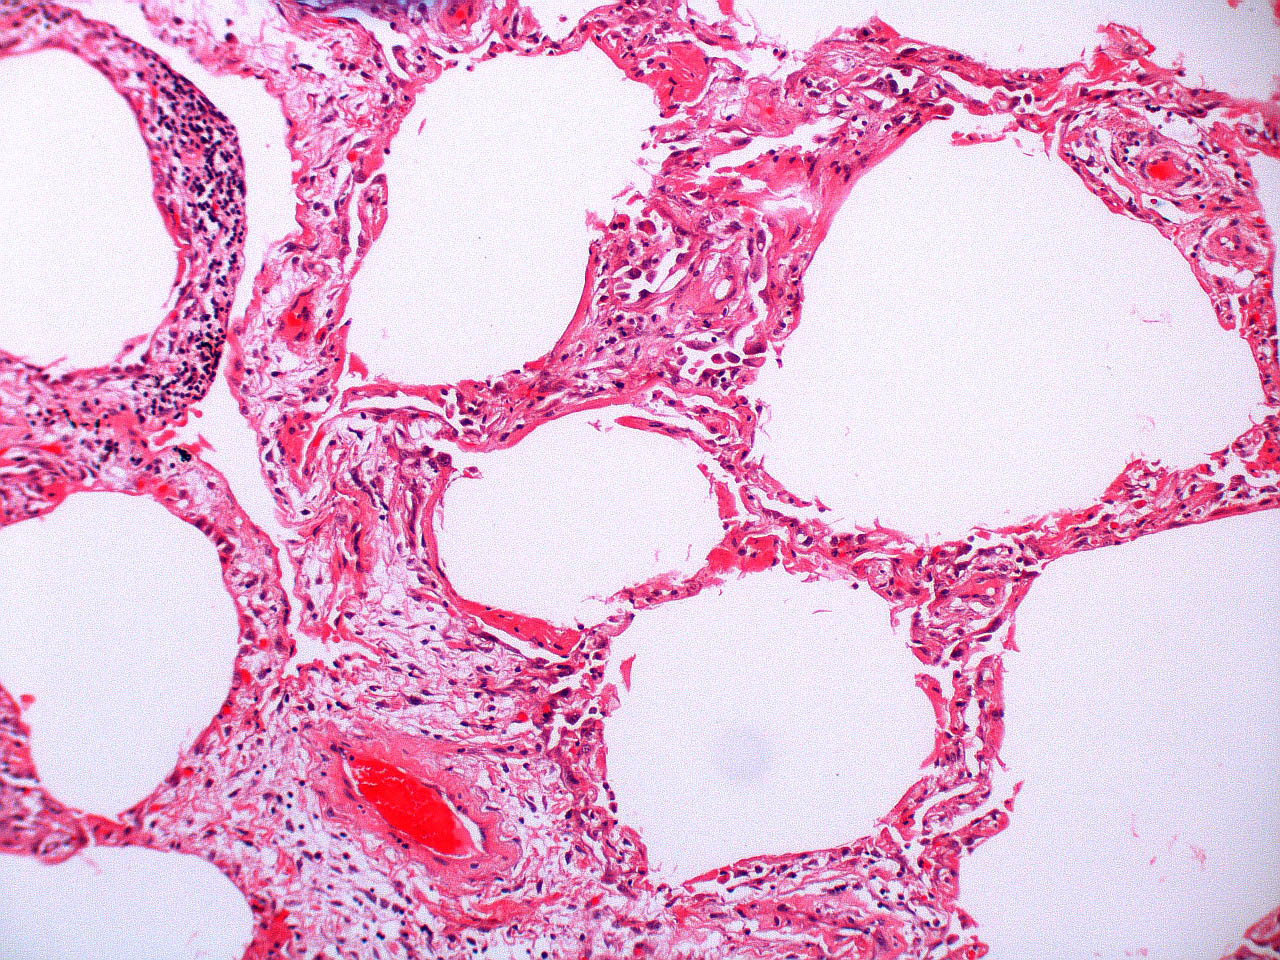

Microscopic (histologic) description

- Histopathology of DAD progresses from exudative (acute) phase through proliferative / organizing (subacute) phase to chronic fibrotic phase roughly corresponding to the period of ARDS (Am J Pathol 1976;85:209, Arch Pathol Lab Med 2010;134:719, Clin Chest Med 2000;21:435, N Engl J Med 2000;342:1334)

- Proliferative / organizing (subacute) phase

- Alveolar change

- Remnants of hyaline membrane with or without organization

- Interstitial and intra-alveolar proliferation of myofibroblasts

- Lymphocytic infiltration

- Epithelial change

- Proliferation / hyperplasia of type II pneumocytes

- Vascular change

- Endothelial injury and thromboemboli in arterioles

- Alveolar change

Microscopic (histologic) images

Contributed by Akira Yoshikawa, M.D. and Yale Rosen, M.D.